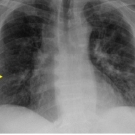

Thomas Eggleston, BS

A 46-year-old man presented to the emergency department with shortness of breath, fluctuating blood pressure, tachycardia, and a mild fever ( 100℉).